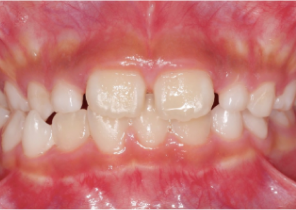

Case Report 1

10 years 0 months old, 18 stages of Invisalign Palatal Expanders

Courtesy of Dr. Sandra Khong Tai

image-card-case1-pre-invis-palatal

Pre Invisalign Palatal Expander Expansion

image-card-case1-post-invis-palatal-expander

Post Invisalign Palatal Expander Expansion